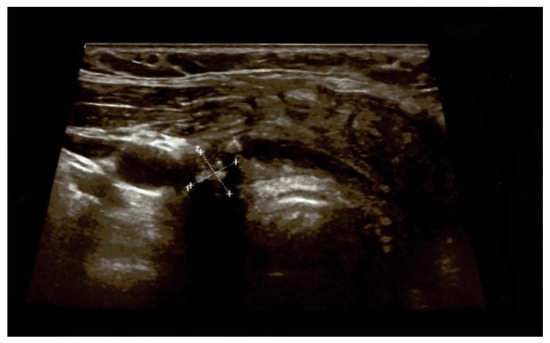

4.1.1. First Admission

4.1.3. Post-Operatory Assessments